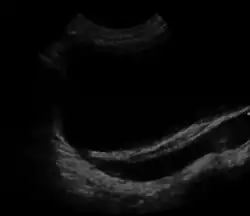

Ultrasound image showing abnormal vesicoureteral junction and dilated distal ureter resulting in primary vesicoureteral reflux (VUR).

Vesicoureteral reflux (VUR), also known as vesicoureteric reflux, is a condition in which urine flows retrograde, or backward, from the bladder into one or both ureters and then to the renal calyx or kidneys.[1][2] Urine normally travels in one direction (forward, or anterograde) from the kidneys to the bladder via the ureters, with a one-way valve at the vesicoureteral (ureteral-bladder) junction preventing backflow. The valve is formed by oblique tunneling of the distal ureter through the wall of the bladder, creating a short length of ureter (1–2 cm) that can be compressed as the bladder fills. Reflux occurs if the ureter enters the bladder without sufficient tunneling, i.e., too "end-on".

Insufficient submucosal length of the ureter relative to its diameter causes inadequacy of the valvular mechanism. This is precipitated by a congenital defect or lack of longitudinal muscle of the portion of the ureter within the bladder resulting in an ureterovesicular junction (UVJ) abnormality.